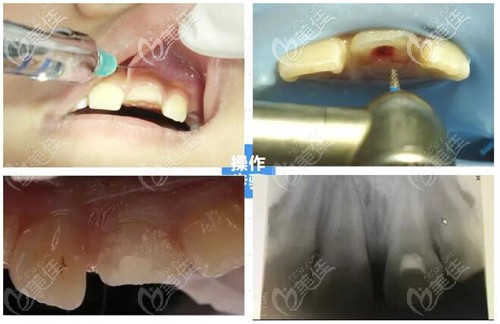

活髓切斷術(shù)是在局部麻木的方式下將牙冠部位的牙髓切斷并且去除,再用蓋髓劑覆蓋在牙髓斷裂上,以此來保留健康的牙齒根髓。

根管治療的方式和目的主要是清理牙齒根管內(nèi)的牙髓炎癥和壞死物質(zhì),通過適當(dāng)消毒充填根管達(dá)到牙髓的治療的效果,但主要是戰(zhàn)隊牙髓壞死不能保留活髓的情況下進(jìn)行治療。

親,做根管治療還是活髓切斷術(shù)得看你的牙髓情況。如果只是門牙折斷但是牙髓健康,修復(fù)辦法是活髓切斷術(shù)+斷冠再接術(shù),對牙齒折斷的部位保留健康牙髓,這樣牙髓健康,牙齒才能更好地維持,手術(shù)價格一般在500元起。

如果牙髓感染、病變就做根管治療,對牙齒炎癥消除,治療費用一般是300元起,一般需要2-4次治療才能完成。我覺得這兩個無論哪一個你得看醫(yī)生技術(shù),手術(shù)技術(shù)好兩項都效果都不錯,你參考下我的建議。